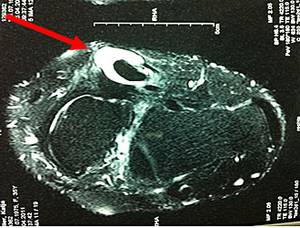

Abb.1: Die MRT zeigt eine chronische Entzündung der Sehne mit Erguss (Pfeil).

Der Knick-Senkfuß beim Erwachsenen entwickelt sich in der Regel durch eine schmerzhafte Insuffizienz der M. Tibialis posterior Sehne. Die Sehne verläuft an der Innenseite unter den Fuß und stützt das Fußlängsgewölbe ab. Sie sorgt beim Gehen für die notwendige Stabilität um sich richtig abstoßen zu können. Insbesondere Übergewicht und Verschleiß dieser Sehne führen zum Bild der klassischen Knick-Senkfußdeformität. Es kommt zu kleinen Teileinrissen auf dem Boden einer chronischen Tendinitis (Sehnenentzündung) oder Tenosynovitis (Sehnenschleimhautentzündung).

Ein akutes Trauma mit kompletten Riss der Sehne mit nachfolgendem Kraftverlust sind die Ausnahme.